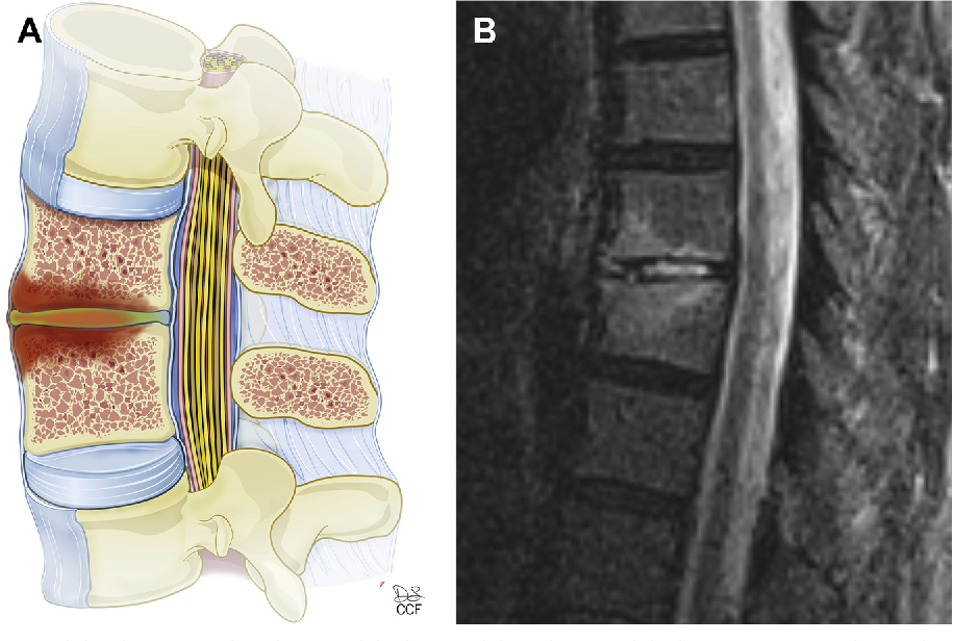

3. Epidural Abscess:

– Accumulation of pus between the spinal cord and the vertebrae.

– Requires urgent medical intervention.

– MRI: The gold standard for diagnosing spinal infections, providing detailed images of the spine and surrounding tissues.